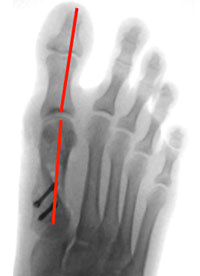

hallux-operation-eine-100-prozentige-sache-1

Abb. 1

Hallux valgus Fehlstellung

a) Abductor

b) Flexor Hallucis

c) Extensor Hallucis Longus

d) Adductor

Abb. 2

Gelenknahe Korrektur